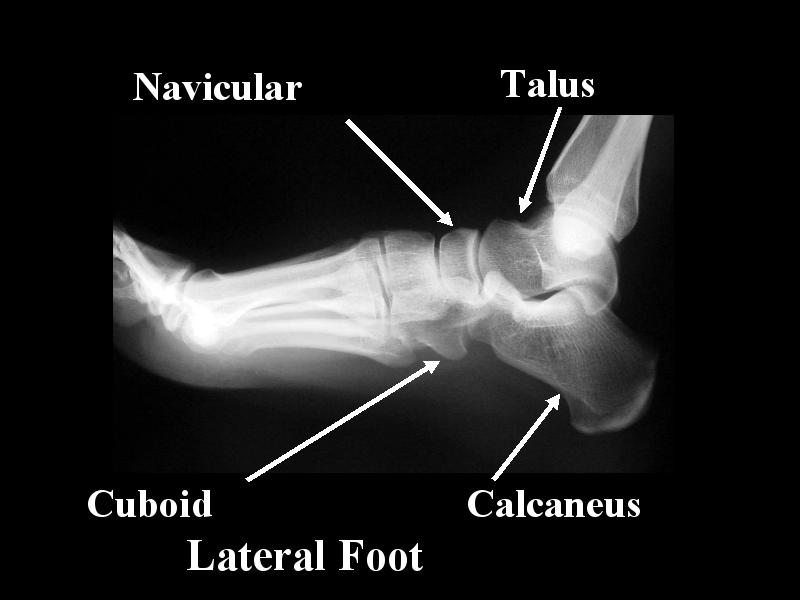

MS 52 LAT FOOT